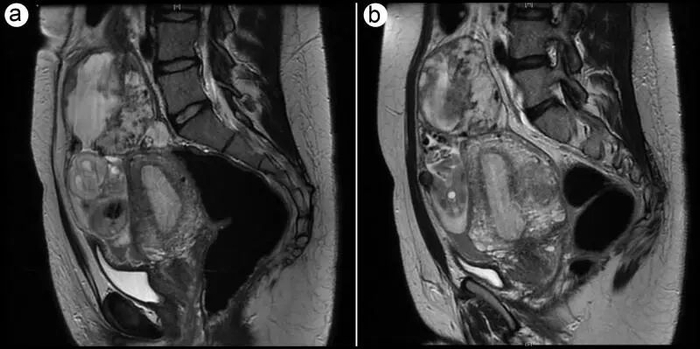

一名37岁女性剧烈腹痛、腹胀10天,去医院急诊。医生惊讶地发现,她的腹腔而非子宫内,有一个活胎,预计怀孕已有23周。经过治疗,孕29周时,她的孩子顺利降生。分娩近3个月后,母子顺利出院。

接诊医生整理她的病历,于近日发布在《新英格兰医学杂志》(NEJM)“临床医学图像”栏目。文章有颇多“看点”,包括:腹腔妊娠极为罕见,母子平安的更是凤毛麟角。

正下方“星号”位置为宫腔;上方“黑色箭头”位置为腹腔妊娠胎儿。图源/N Engl J Med

医生查体认为,其腹部隆起,值得关注。随后的B超检查显示,子宫内膜增厚、子宫增大,但宫腔空虚,疑似异位妊娠约23周。

进一步的核磁共振成像证实了这一推测:胎盘附着在骶骨岬上方腹膜位置,胎儿形态正常、有胎心搏动,可诊断为“腹腔异位妊娠”。骶骨岬位于卵巢上方、靠近输卵管位置,距离子宫较远。